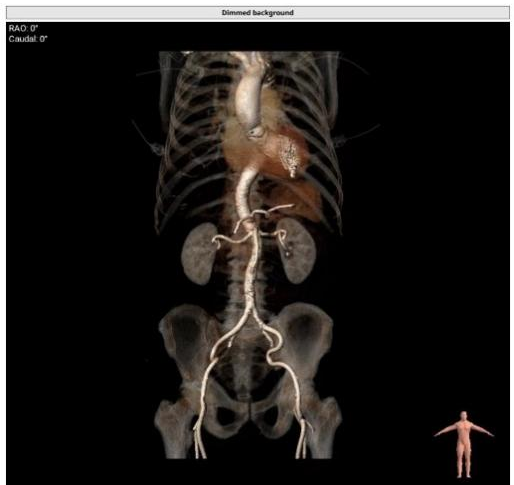

患者全麻,气管插管。经左侧股动脉作为辅入路,将6F猪尾巴导管送至无冠窦窦底,右股动脉作为主入路,右侧股动脉作为主入路,置入18F大鞘,先行主动脉根部造影,可见术前有轻中度返流,行24mm球囊进行预扩,无瓣周漏,无明显腰征,双侧冠脉血流通畅,决定按计划选择27# VitaFlow Liberty™瓣膜,在王建安教授的线上指导、刘先宝教授的现场支持下,将瓣膜释放至功能位,再次造影发现瓣膜位置偏高,遂进行回收,再次释放,最终脱钩,再次造影确认瓣膜位置及形态良好,压差从术前的80mmHg降低至2mmHg,无瓣周漏。

在多学科协作下,嘉兴市第一医院心血管内科完成经导管主动脉瓣膜置入(TAVR)手术,经过2个小时紧张有序的操作,手术取得圆满成功,患者苏醒后顺利转入普通病房,术后第四天即顺利出院。

翟昌林教授说到,相比传统开放手术,经股动脉的TAVR手术,不需要体外循环,不需要打开胸骨,几乎没有明显的失血,麻醉时间更短,创伤小、恢复快。